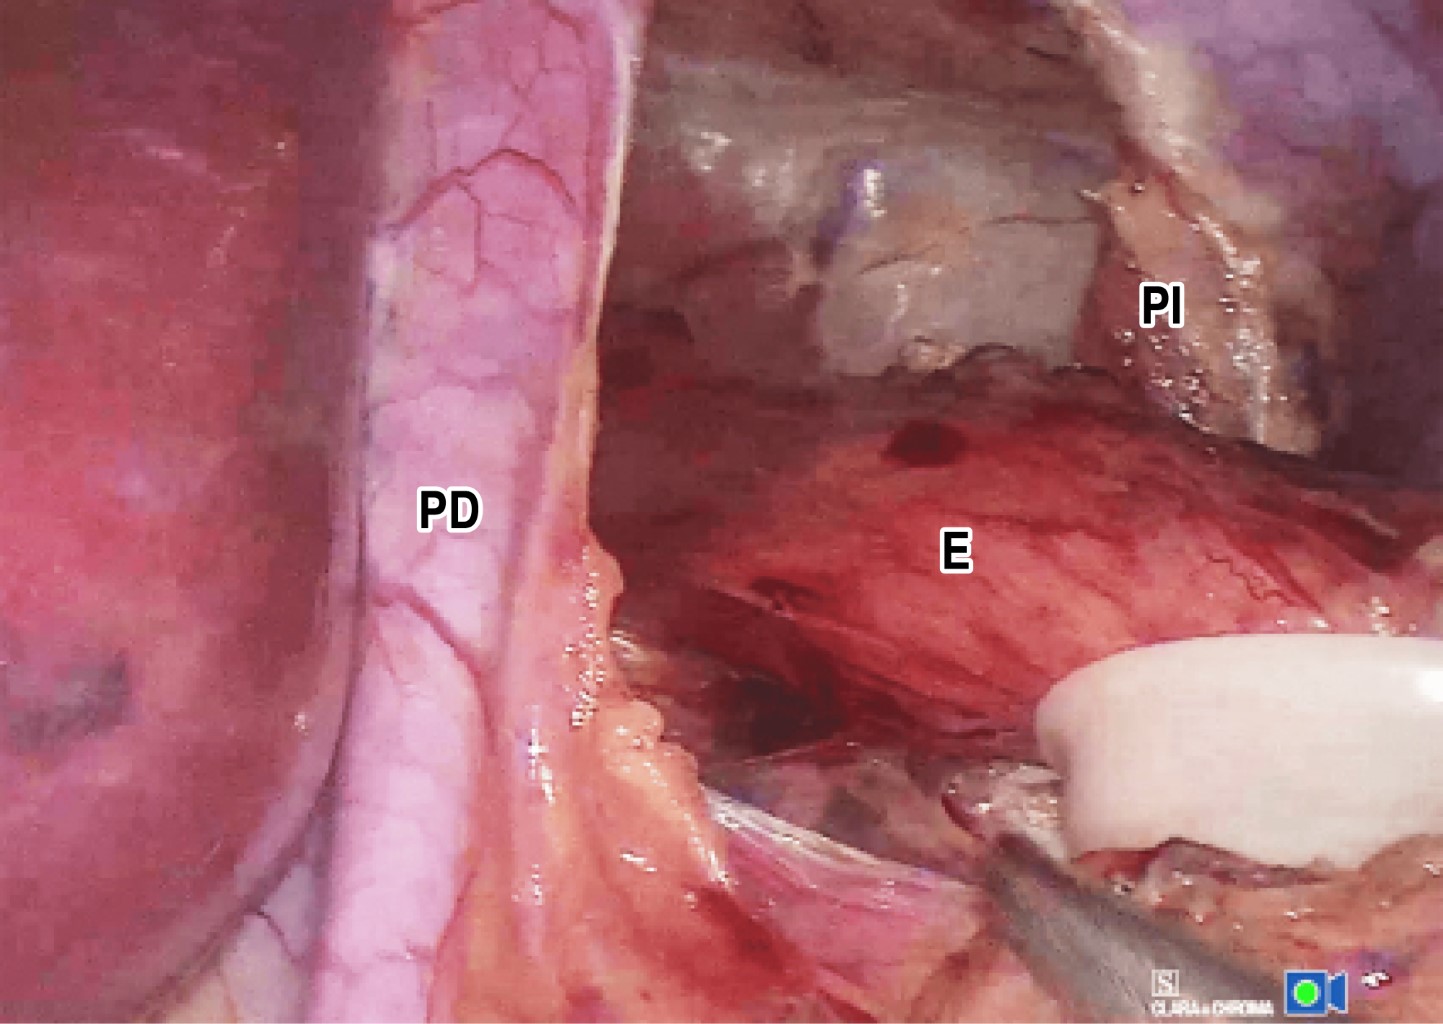

What were the benefits of preserving the phrenoesophageal membrane and diaphragmatic transversalis fascia while performing laparoscopic Nissen fundoplication? A comparative study

Introduction and objectives: laparoscopic fundoplication involves the dissection of the phrenoesophageal membrane (PEM) and the diaphragmatic transversalis fascia (DTF). We propose modifying this technique by preserving the anatomical structures involved in esophageal fixation to reduce surgical trauma, decrease postoperative pain, dyspeptic syndrome and dysphagia, and evaluate the main outcomes of this technique. Material and methods: a comparative, prospective, observational study was conducted in a private hospital in Mexico City from August 2018 to January 2022, including patients diagnosed with gastroesophageal reflux disease (GERD) due to lower esophageal sphincter (LES) incompetence or hiatal hernia confirmed by endoscopic, radiological, and manometric evaluation. These patients were treated with a modified laparoscopic Nissen procedure that preserved the PEM and DTF and were followed up for one year. The following variables were considered: gender, age, weight, number of surgical sutures in fundoplication, hernia size in centimeters, bleeding, surgical time, comorbidities, ligation of short vessels, length of hospital stay, postoperative pain, and postoperative dysphagia. Results: during the study, 45 patients underwent laparoscopic fundoplication. In 24 patients, the PEM and DTF were preserved, forming the study group. All of these patients had type I hiatal hernia with LES incompetence. The remaining 21 patients did not have the membrane preserved. All patients showed significant improvement in terms of postoperative pain and dysphagia. Conclusions: preservation of the PEM and DTF is a technically feasible and safe modification of the Nissen procedure for type I hiatal hernia, with good results.